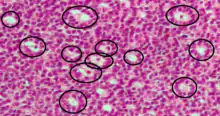

Call–Exner bodies, giving a follicle-like appearance, are small eosinophilic fluid-filled punched out spaces between granulosa cells.[1] The granulosa cells are usually arranged haphazardly around the space.

They are pathognomonic for granulosa cell tumors.

Histologically, these tumors consists of monotonous islands of granulosa cells with "coffee-bean" nuclei. That same nuclear groove appearance noted in Brenner tumour, an epithelial-stromal ovarian tumor distinguishable by nests of transitional epithelial cells (urothelial) with longitudinal nuclear grooves (coffee bean nuclei) in abundant fibrous stroma.[2][3]

They are composed of membrane-packaged secretion of granulosa cells and have relations to the formation of liquor folliculi which are seen among closely arranged granulosa cells.